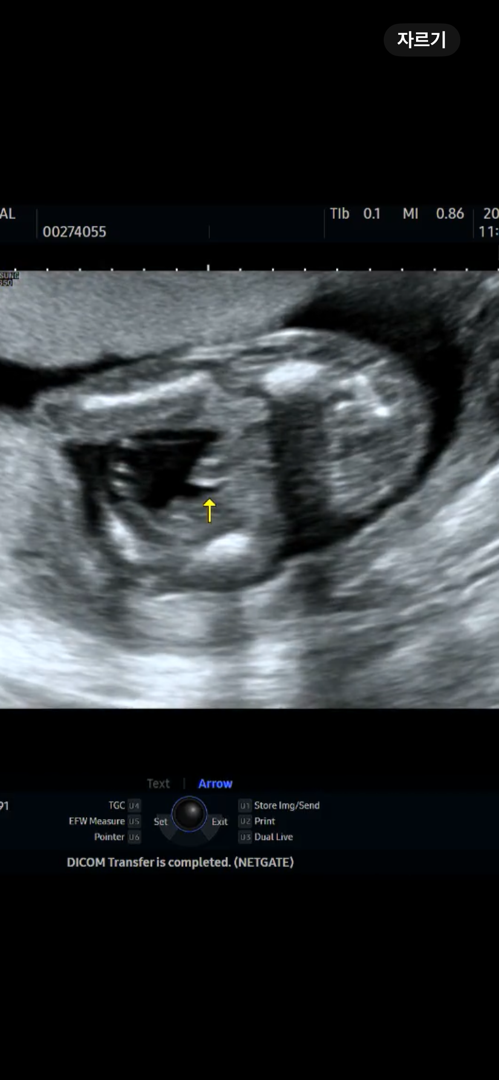

17주 성별확인

이미 12주때부터 80% 아들확정 13주에 그냥 아들 탕탕이였는데..! 첫째 아들도 이정도로 확실한느낌이 아니였는데 기대말라고 이렇게 큰건지...아들확정받았는데 아들로 받아들여야겟죠?ㅎㅎㅎ